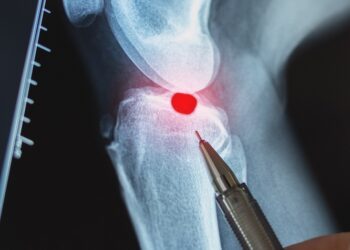

Skaityti daugiauDetailsFibrozinė displazija – tai reta kaulų liga, kuomet normalų kaulinį audinį pakeičia skaidulinis, į randą panašus audinys. Tokie pakitimai silpnina...

Skaityti daugiauDetailsFibrosarkoma yra reta ir agresyvi vėžio forma, dažniausiai susiformuojanti giliai kūno minkštuosiuose audiniuose, tokiuose kaip kojos, žastas, keliai ar liemuo....